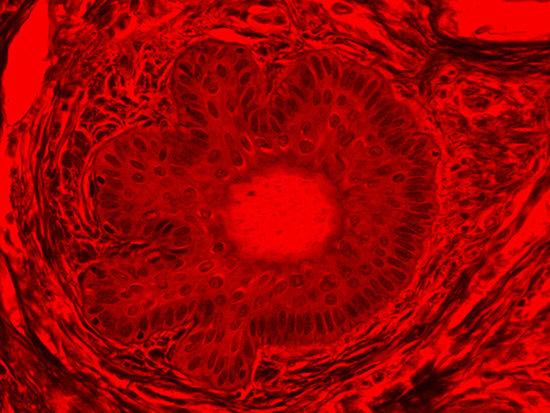

Figure 1: Brightfield Image of Dermal Tissue

When comparing Figures 1 and 2, the visual differences are significant. A brightfield image is formed with the illumination source below the sample, and then transmitted light propagates through the sample to the sensor forming a bright, white background with sharp color. A darkfield image is formed by directing light at an oblique angle through the sample, forming a hollow cone of light which is collected by the objective. Darkfield illumination typically yields a dark background with sharp color, but in the case of Figure 2, the collagen and muscle fibers interfered with the light path and caused a blur of light and color. The dark background is hardly evident and only two distinct colors are visible. When analyzing histological stains, brightfield illumination is the preferred technique for lighting a sample.

When comparing Figure 3 with Figure 4, there is once again a significant visual difference. The most obvious feature is the change in color from green to red due to a different hardcoated filter being positioned in the optical path. The less obvious difference is the varying contrast levels caused by the filters at specific regions of the dermal tissue. For example, Figure 3 exhibits a distinct ring at the central region of the cell with additional matter within. In Figure 4, the ring is extremely faint and the internal matter is not visible. With that said, the cell and surrounding dense materials are more evident in Figure 3, whereas the muscle fibers and collagen are more pronounced in Figure 4.